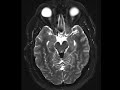

Tectal Plate Lipoma

These images show a T1 hypertense, T2 FLAIR hyperintense mass of the tectal plate which becomes hypointense on T2 fat-saturated images compatible with a lipoma. High resolution sagittal CISS imaging shows the cerebral aqueduct to be patent. About half of intracranial lipomas are associated with the corpus callosum with suprasellar and tectal locations making up the second and third most common locations. These masses are usually found incidentally and the tubulonodular type in the pericallosal location may demonstrate rim calcification and be seen with anomalies of the corpus callosum.